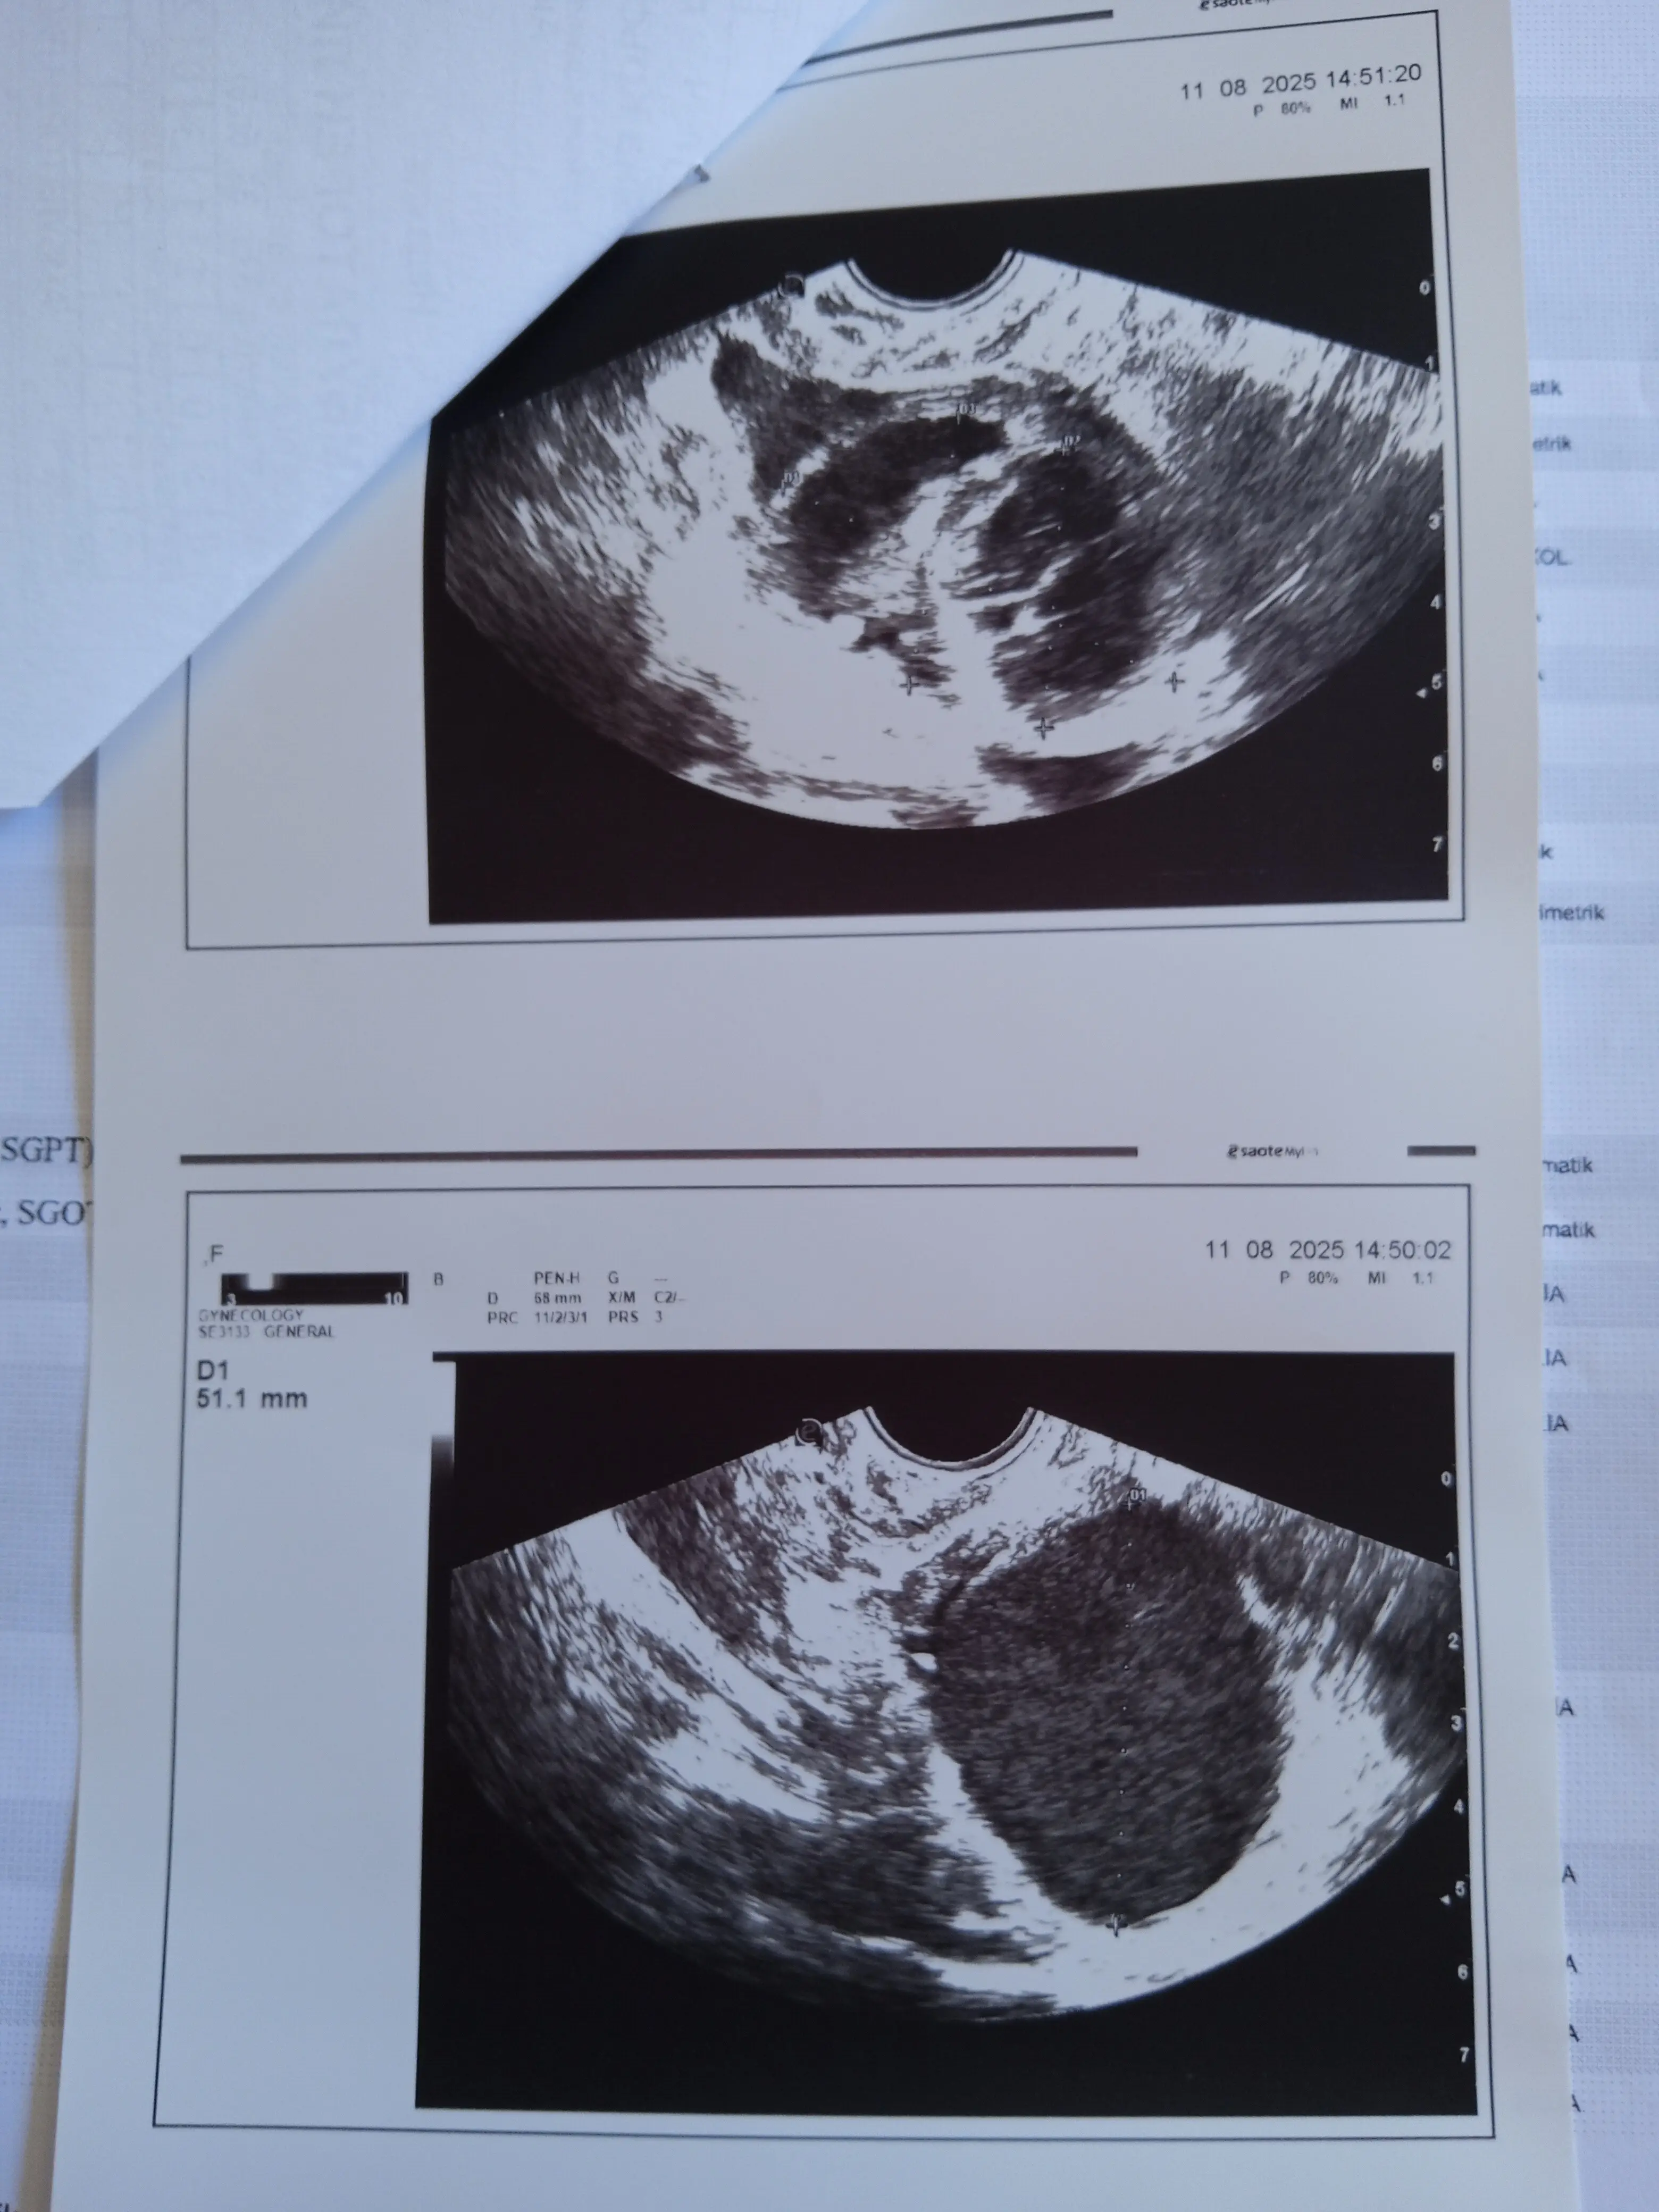

След направен нов преглед от АГ специалист,се оказа че спешно трябва да ми се отстранят яйчниците поради големите кисти и повишен туморен маркер СЕА,може да видите в качените снимки..

After a new examination by an OBGYN specialist, it turned out that I urgently need to remove my ovaries due to large cysts and elevated tumor marker CEA, you can see in the uploaded photos..